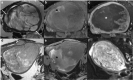

Although rare, uterine sarcoma is a diagnosis that no one wants to miss. Often benign leiomyomas (fibroids) and uterine sarcomas can be differentiated due to the typical low T2 signal intensity contents and well-defined appearances of benign leiomyomas compared to the suspicious appearances of sarcomas presenting as large uterine masses with irregular outlines and intermediate T2 signal intensity together with possible features of secondary spread. The problem is when these benign lesions are atypical causing suspicious imaging features. This article provides a review of the current literature on imaging features of atypical fibroids and uterine sarcomas with an aide-memoire BET1T2ER Check! to help identify key features more suggestive of a uterine sarcoma.